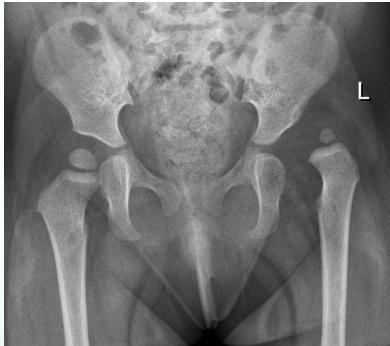

Radiographic Stages:

-

Initial/ Bone Death Stage - May initially appear normal on x-ray

- Increased density followed by collapse

Revascularization and Repair Stage - Reduced density and fragmentation on x-ray

Distortion and Remodeling Stage - Distortion, flattening (coxa plana)

- Enlargement (coxa magna) with partial uncoverage

Radiological Progression:

Progression: Sclerosis → Collapse → Fragmentation → Remodeling

Imaging Examples: